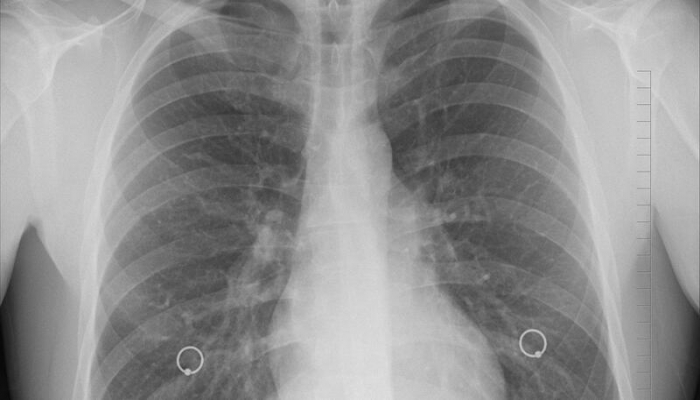

Koronavirusdan sonra ağciyərlərin bərpa dövrü nə qədərdir?

Koronavirusdan sonra ağciyərlərin bərpa dövrü altı aydan iki ilə qədər davam edə bilər, ancaq bədənin bu problemin öhdəsindən daha sürətli gəlməsinə kömək edə bilərsiniz.